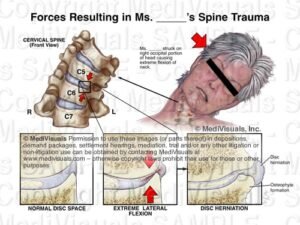

Освен болка, пациентите могат да изпитват изтръпване, мравучкане или намалена мускулна сила в ръката. Симптомите често се появяват при притискане на нерв вследствие на дискова херния, дегенеративни промени или стесняване на нервните отвори между прешлените.

• дискова херния във врата

Тези промени могат да доведат до натиск върху нервния корен и да предизвикат болка и неврологични симптоми.

• дискова херния във врата

Тези промени могат да доведат до дразнене или притискане на нервния корен и да причинят болка, изтръпване или слабост в ръката.